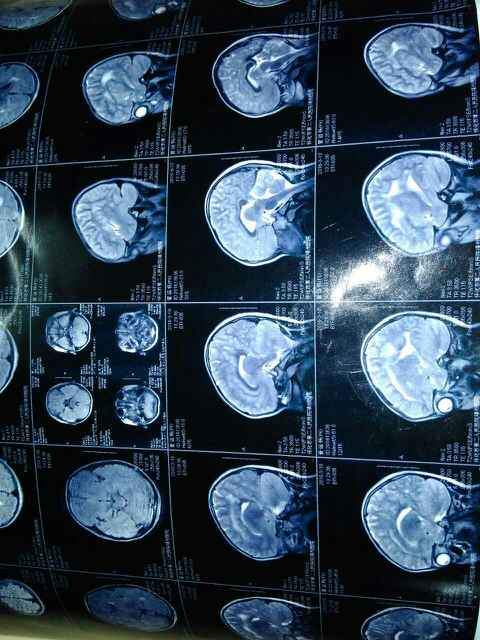

小妹今年六岁,身体看着挺健康的,没什么病痛,只是三岁左右查出有远视眼,视力不好。但前几天查脑部核磁,医生说可能有问题。万分交集,在此求助万能的虫友,万分感谢! 发自小木虫Android客户端 |